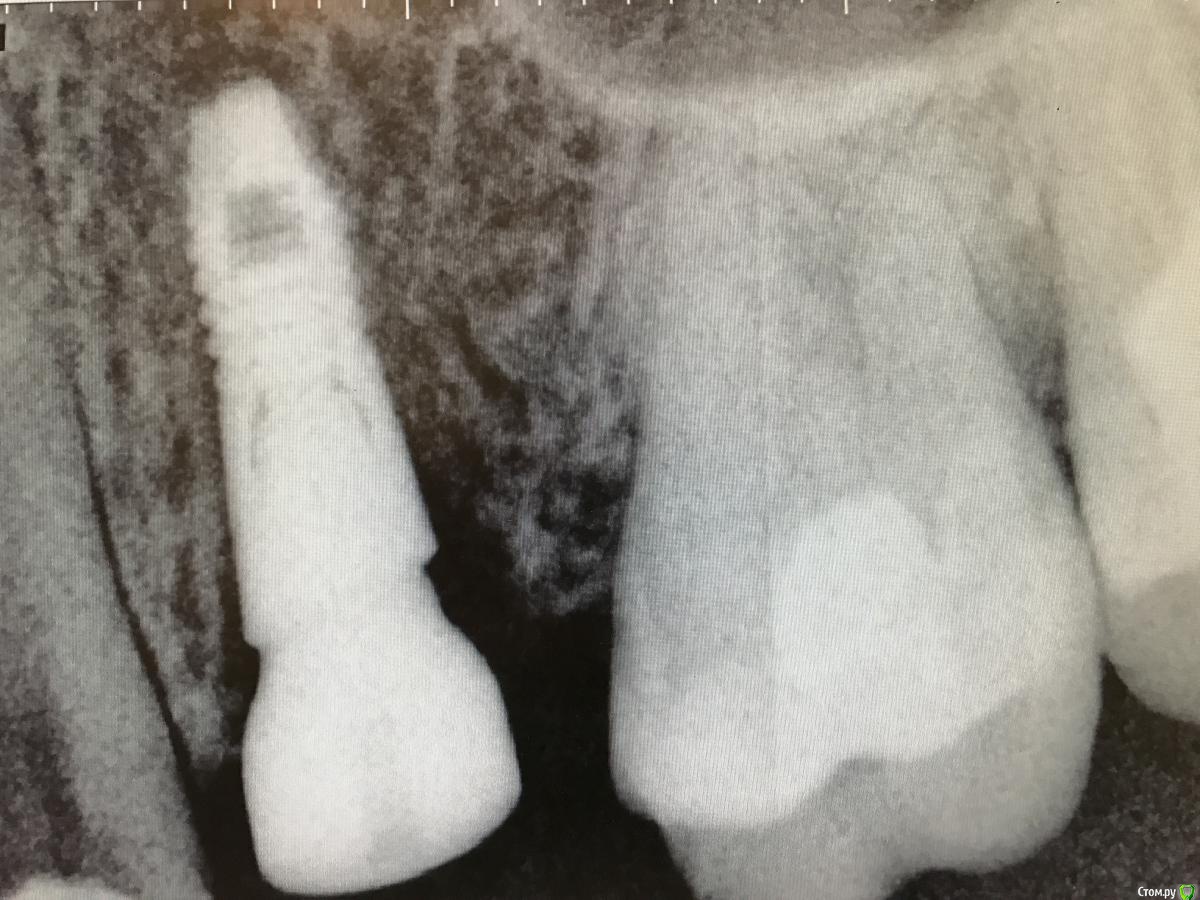

колесников Опубликовано 25 февраля, 2017 Поделиться Опубликовано 25 февраля, 2017 Здравствуйте коллеги! Представляю вашему вниманию этот клинический случай.В ноябре 2016 обратилась пациентка с жалобами на выпадение ортопедической конструкции в обл 24. Объективно: корни 24 не состоятельны. ,на десневом крае в проекции 24 свищевой ход с гнойным отделяемым.На КТ резорбция вестибулярной компактной пластинки и деструкция костной ткани в области щёчного корня.Приняв во внимание крайне негативное отношение пациентки к каким бы то ни было хирургическим вмешательствам и высоким эстетическим требованиям,было решено пойти на немедленную имплантацию .Снимки в день вмешательства,через 7,14 дней и 3мес.Имплант Astra tech profile 4.5х11мм. Сст с бугра вестибулярно. Вместо графта губки Коллапола (не вспомню причину,либо не было в наличии,либо отказ пациента). 15 Ссылка на комментарий

колесников Опубликовано 12 июня, 2017 Автор Поделиться Опубликовано 12 июня, 2017 Контрольное кт спустя 3 мес. Откуда-то наросло 2мм у шейки. Ссылка на комментарий

Doctor Vlad Опубликовано 13 июня, 2017 Поделиться Опубликовано 13 июня, 2017 Откуда-то наросло 2мм у шейки. да видимо графт был, причем не коллапон коллагеновый а костная стружка, даже по первым снимкам после операции там чтото рыхлое торчит. Ссылка на комментарий